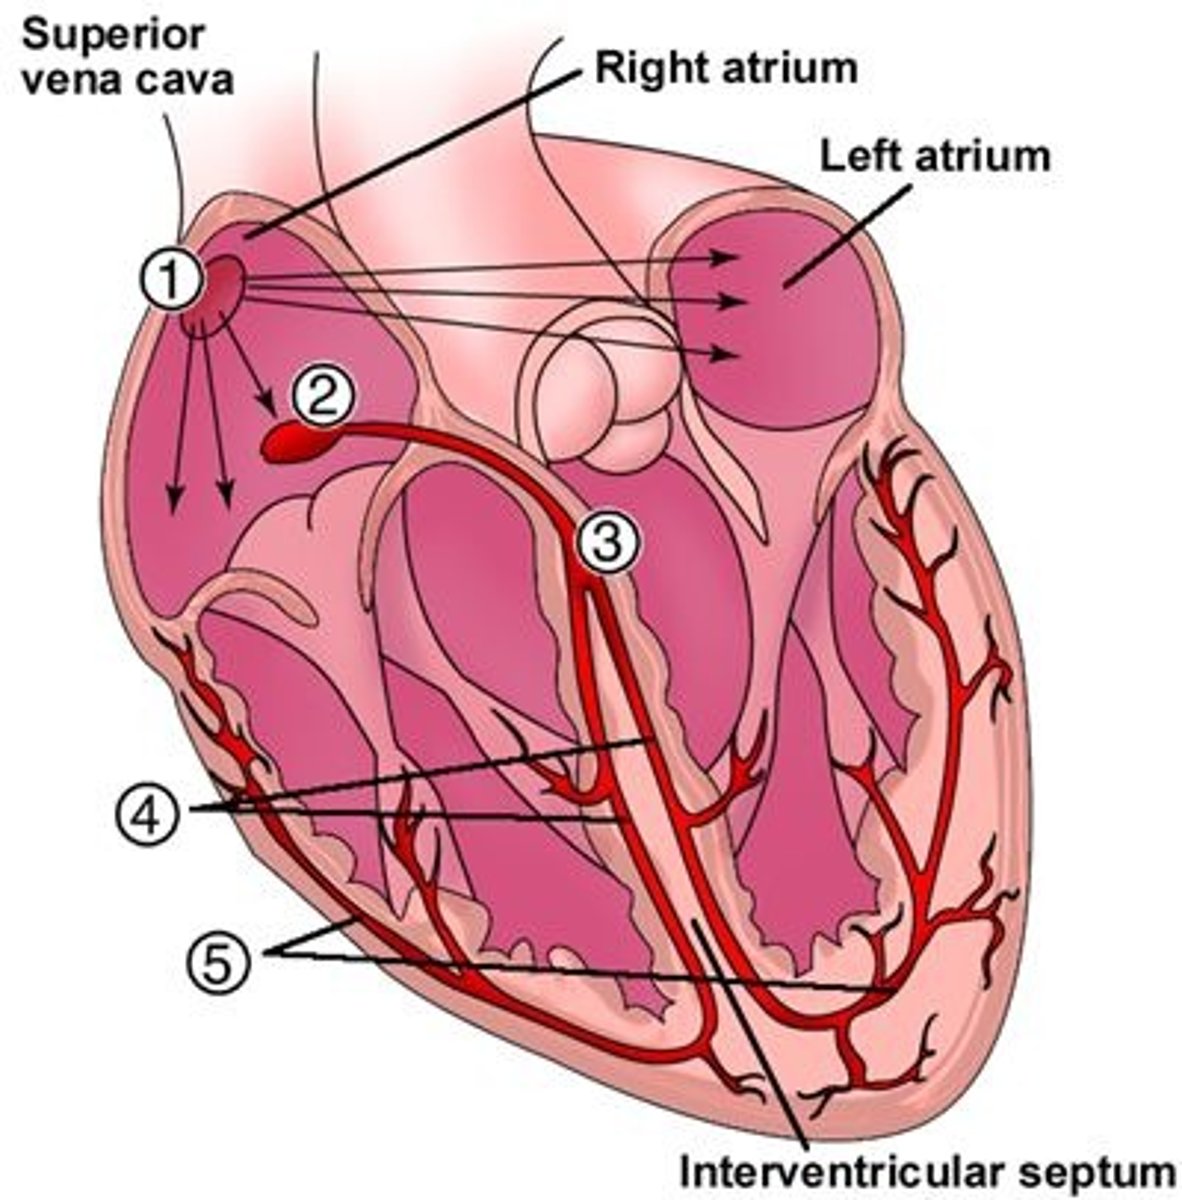

Coronary arteries (right (A) and left(D))

First branch off the base of the aorta

Blocked when aortic semilunar valve opens

Supplies blood to the heart muscles

Marginal artery (C) and Posterior Interventricular artery (B)

Branches of right coronary artery

Anterior Interventricular artery (F) and Circumflex artery (E)

Branches of the left coronary artery

Sinoatrial (SA) node -> Atrioventricular (AV) node -> Atrioventricular Bundle or Bundle of His -> Right and Left Bundle Branches -> Purkinje Fibers

Intrinsic conduction system pathway